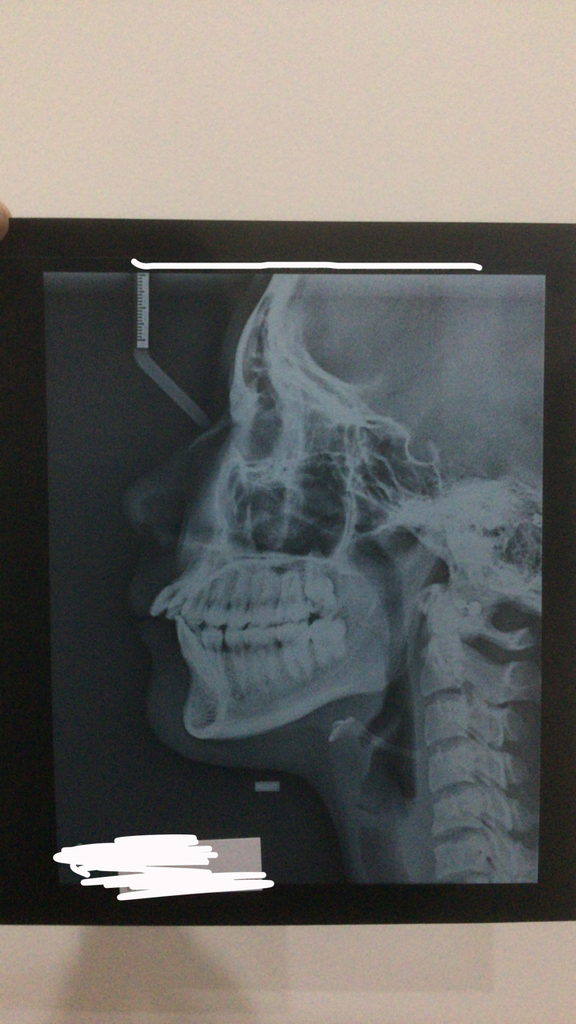

Okay so I went to my ortho today, he was looking at my teeth, said all the right things (crowding, 9mm overjet, severe class 2 malocclusion, crossbite),

I also told him I have sleep apnea and I did 2 scans but here’s what he told me, he told me he can’t offer me MARPE and that my two options would be

Anyways I underwent an OPG and a Cenograph, these are the results.